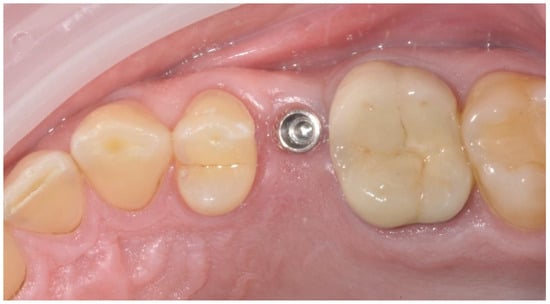

2.2. Surgical Procedures

2.3. Prosthetic Protocol